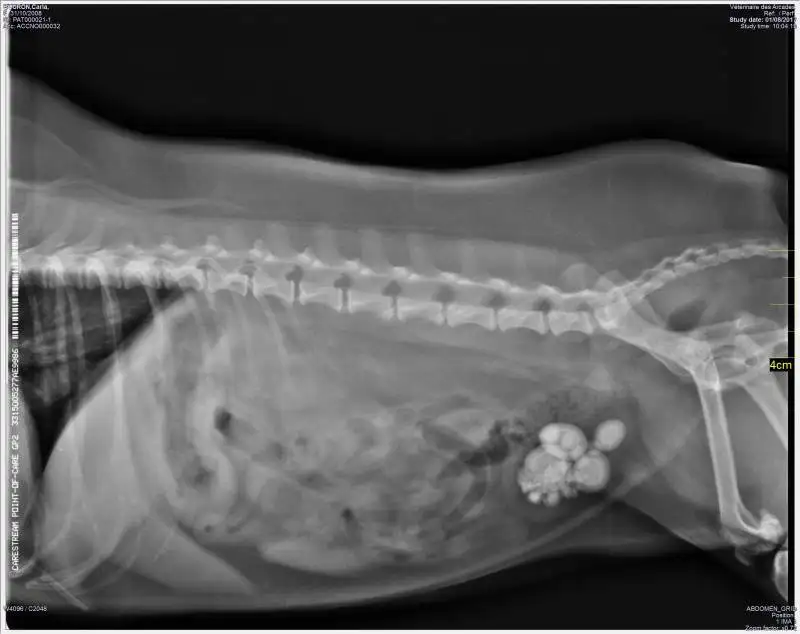

Elle peut être indiquée en cas d'urgence (occlusion, hernie étranglée, hémorragie interne, etc.), ou bien être programmée (calculs biliaires, rénaux, vésicaux; tumeurs; ingestion d'un corps étranger; etc.).